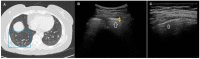

Transthoracic ultrasound (TUS) is a readily available imaging tool that can provide a quick real-time evaluation. The aim of this preliminary study was to establish a complementary role for this imaging method in the approach of interstitial lung diseases (ILDs). TUS examination was performed in 43 consecutive patients with pulmonary fibrosis and TUS findings were compared with the corresponding high-resolution computed tomography (HRCT) scans. All patients showed a thickened hyperechoic pleural line, despite no difference between dominant HRCT patterns (ground glass, honeycombing, mixed pattern) being recorded (p > 0.05). However, pleural lines' thickening showed a significant difference between different HRCT degree of fibrosis (p < 0.001) and a negative correlation with functional parameters. The presence of >3 B-lines and subpleural nodules was also assessed in a large number of patients, although they did not demonstrate any particular association with a specific HRCT finding or fibrotic degree. Results allow us to suggest a complementary role for TUS in facilitating an early diagnosis of ILD or helping to detect a possible disease progression or eventual complications during routine clinical practice (with pleural line measurements and subpleural nodules), although HRCT remains the gold standard in the definition of ILD pattern, disease extent and follow-up.